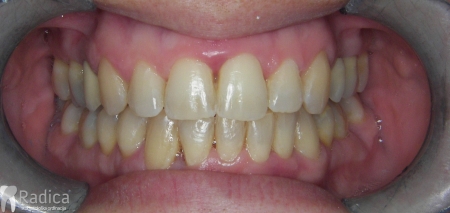

U sljedećem primjeru je fiksna ortodontska terapija rađena samo u donjoj čeljusti. Nakon toga pacijent je upućen svom stomatologu koji je napravio nove protetske radove u gornjoj i donjoj čeljusti.

Na sljedećoj slici mogu se vidjeti početak i kraj ortodontske terapije. Pacijentica je upućena od svog stomatologa nakon što nije bila zadovoljna izgledom osmjeha i odnosom zuba i gingive u privremenom protetskom radu. Napravljena je ortodontska terapija samo u gornjoj čeljusti a nakon toga novi privremeni protetski rad.